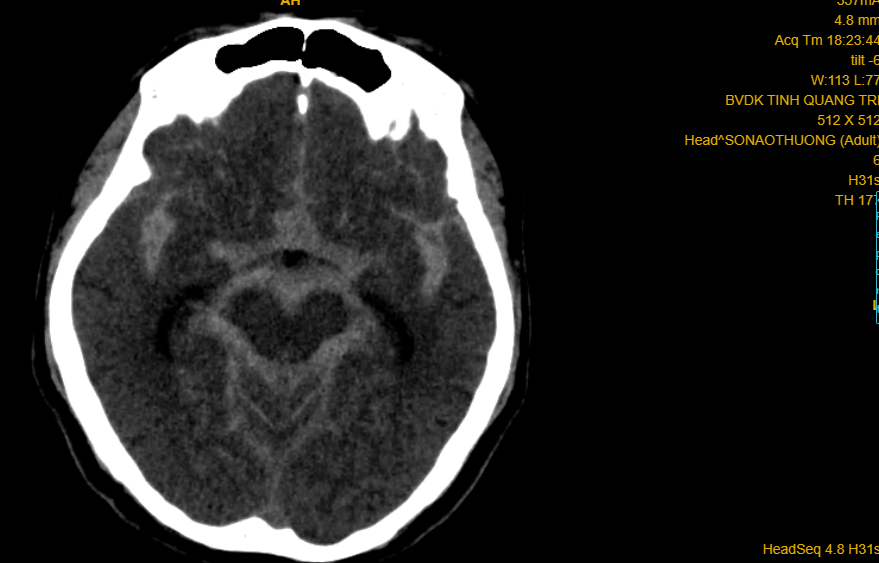

Phim CT-scan trường hợp số 01 (doanh nhân 57 tuổi) xuất huyết não